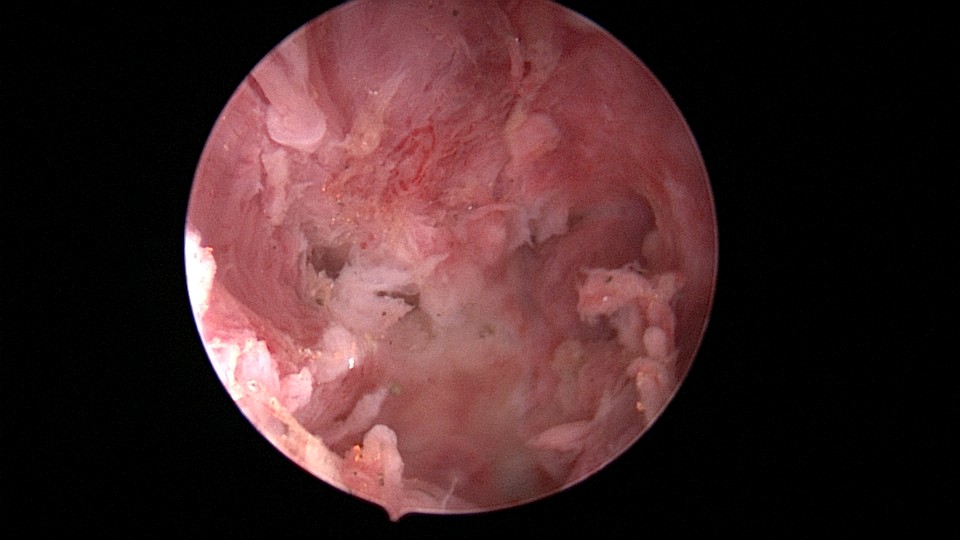

患者49岁,G1P1,顺产1次。安环13年,月经紊乱1月,外院取环失败。B超提示O型环嵌顿,宫腔镜见宫颈管及宫腔组织充血,宫腔广泛粘连,节育环嵌顿、扭曲,异物钳配合中弯钳拉出节育环,环变形、断裂,宫壁节育环嵌顿处见割裂痕迹,无出血,检查宫腔各部,无节育环残留。

图片发自160App